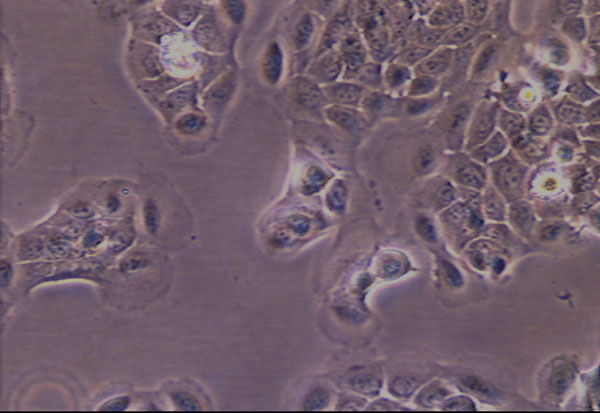

Figure 3 a:

Phase contrast,